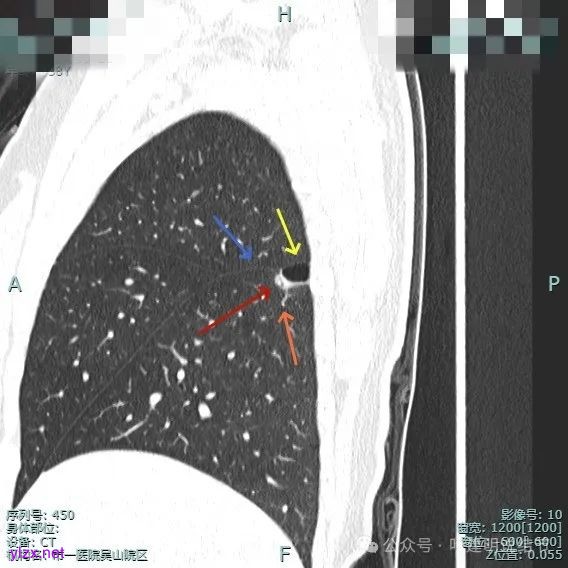

血管走向病灶,囊壁略不均。

此层见囊壁有较明显实性成分,血管进入明显。叶间裂侧平直。

混合密度,收缩力不明显,血管进入明显。

囊壁混合密度,整体轮廓清。

表面不平,血管进入,囊壁厚薄不均,紧贴叶间裂。